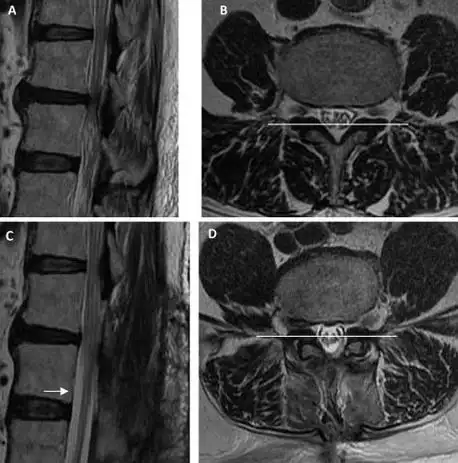

腰椎管狭窄分型